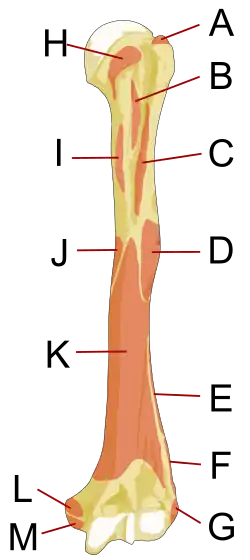

Upper extremity

The upper or proximal extremity of the humerus consists of the bone's large rounded head joined to the body by a constricted portion called the neck, and two eminences, the greater and lesser tubercles.

Head

The head (caput humeri) is nearly hemispherical in form. It is directed upward, medialward, and a little backward, and articulates with the glenoid cavity of the scapula to form the glenohumeral joint (shoulder joint). The circumference of its articular surface is slightly constricted and is termed the anatomical neck, in contradistinction to a constriction below the tubercles called the surgical neck which is frequently the seat of fracture. Fracture of the anatomical neck rarely occurs.[2] The diameter of the humeral head is generally larger in men than in women.

Anatomical neck

The anatomical neck (collum anatomicum) is obliquely directed, forming an obtuse angle with the body. It is most prominent in the lower half of its circumference, while in the upper half, it is represented by a narrow groove separating the head from the tubercles. The line separating the head from the rest of the upper end is called the anatomical neck. It affords attachment to the articular capsule of the shoulder-joint, and is perforated by numerous vascular foramens. Fracture of the anatomical neck rarely occurs.[2]

The anatomical neck of the humerus is an indentation distal to the head of the humerus on which the articular capsule attaches.

Surgical neck

The surgical neck is a narrow area distal to the tubercles that is a common site of fracture. It makes contact with the axillary nerve and the posterior humeral circumflex artery.

Greater tubercle

The greater tubercle (tuberculum majus; greater tuberosity) is a large, posteriorly placed projection that is placed laterally. The greater tubercle is where supraspinatus, infraspinatus and teres minor muscles are attached. The crest of the greater tubercle forms the lateral lip of the bicipital groove and is the site for insertion of pectoralis major.

The greater tubercle is just lateral to the anatomical neck. Its upper surface is rounded and marked by three flat impressions: the highest of these gives insertion to the supraspinatus muscle; the middle to the infraspinatus muscle; the lowest one, and the body of the bone for about 2.5 cm. below it, to the teres minor muscle. The lateral surface of the greater tubercle is convex, rough, and continuous with the lateral surface of the body.[2]

Lesser tubercle

The lesser tubercle (tuberculum minus; lesser tuberosity) is smaller, anterolaterally placed to the head of the humerus. The lesser tubercle provides insertion to subscapularis muscle. Both these tubercles are found in the proximal part of the shaft. The crest of the lesser tubercle forms the medial lip of the bicipital groove and is the site for insertion of teres major and latissimus dorsi muscles.

The lesser tuberosity, is more prominent than the greater: it is situated in front, and is directed medialward and forward. Above and in front it presents an impression for the insertion of the tendon of the subscapularis muscle.[2]

Bicipital groove

The tubercles are separated from each other by a deep groove, the bicipital groove (intertubercular groove; bicipital sulcus), which lodges the long tendon of the biceps brachii muscle and transmits a branch of the anterior humeral circumflex artery to the shoulder-joint. It runs obliquely downward, and ends near the junction of the upper with the middle third of the bone. In the fresh state its upper part is covered with a thin layer of cartilage, lined by a prolongation of the synovial membrane of the shoulder-joint; its lower portion gives insertion to the tendon of the latissimus dorsi muscle. It is deep and narrow above, and becomes shallow and a little broader as it descends. Its lips are called, respectively, the crests of the greater and lesser tubercles (bicipital ridges), and form the upper parts of the anterior and medial borders of the body of the bone.[2]

Shaft

The body or shaft of the humerus is triangular to cylindrical in cut section and is compressed anteroposteriorly. It has 3 surfaces, namely:

- Anterolateral surface: the area between the lateral border of the humerus to the line drawn as a continuation of the crest of the greater tubercle. The antero-lateral surface is directed lateralward above, where it is smooth, rounded, and covered by the deltoid muscle; forward and lateralward below, where it is slightly concave from above downward, and gives origin to part of the brachialis. About the middle of this surface is a rough, rectangular elevation, the deltoid tuberosity for the insertion of the deltoid muscle; below this is the radial sulcus, directed obliquely from behind, forward, and downward, and transmitting the radial nerve and profunda artery.

- Anteromedial surface: the area between the medial border of the humerus to the line drawn as a continuation of the crest of the greater tubercle. The antero-medial surface, less extensive than the antero-lateral, is directed medialward above, forward and medialward below; its upper part is narrow, and forms the floor of the intertubercular groove which gives insertion to the tendon of the latissimus dorsi muscle; its middle part is slightly rough for the attachment of some of the fibers of the tendon of insertion of the coracobrachialis muscle; its lower part is smooth, concave from above downward, and gives origin to the brachialis muscle.

- Posterior surface: the area between the medial and lateral borders. The posterior surface appears somewhat twisted, so that its upper part is directed a little medialward, its lower part backward and a little lateralward. Nearly the whole of this surface is covered by the lateral and medial heads of the Triceps brachii, the former arising above, the latter below the radial sulcus.

Its three borders are:

- Anterior: the anterior border runs from the front of the greater tubercle above to the coronoid fossa below, separating the antero-medial from the antero-lateral surface. Its upper part is a prominent ridge, the crest of the greater tubercle; it serves for the insertion of the tendon of the pectoralis major muscle. About its center it forms the anterior boundary of the deltoid tuberosity, on which the deltoid muscle attaches; below, it is smooth and rounded, affording attachment to the brachialis muscle.

- Lateral: the lateral border runs from the back part of the greater tubercle to the lateral epicondyle, and separates the anterolateral from the posterior surface. Its upper half is rounded and indistinctly marked, serving for the attachment of the lower part of the insertion of the teres minor muscle, and below this giving origin to the lateral head of the triceps brachii muscle; its center is traversed by a broad but shallow oblique depression, the spiral groove (musculospiral groove). The radial nerve runs in the spiral groove. Its lower part forms a prominent, rough margin, a little curved from backward, forward the lateral supracondylar ridge, which presents an anterior lip for the origin of the brachioradialis muscle two-thirds above, and extensor carpi radialis longus muscle one-third below, a posterior lip for the triceps brachii muscle, and an intermediate ridge for the attachment of the lateral intermuscular septum.

- Medial: the medial border extends from the lesser tubercle to the medial epicondyle. Its upper third consists of a prominent ridge, the crest of the lesser tubercle, which gives insertion to the tendon of the teres major muscle. About its center is a slight impression for the insertion of the coracobrachialis muscle, and just below this is the entrance of the nutrient canal, directed downward; sometimes there is a second nutrient canal at the commencement of the radial sulcus. The inferior third of this border is raised into a slight ridge, the medial supracondylar ridge, which became very prominent below; it presents an anterior lip for the origins of the brachialis muscle and the pronator teres muscle, a posterior lip for the medial head of the triceps brachii muscle, and an intermediate ridge for the attachment of the medial intermuscular septum.

The deltoid tuberosity is a roughened surface on the lateral surface of the shaft of the humerus and acts as the site of insertion of deltoideus muscle. The posterorsuperior part of the shaft has a crest, beginning just below the surgical neck of the humerus and extends till the superior tip of the deltoid tuberosity. This is where the lateral head of triceps brachii is attached.

The radial sulcus, also known as the spiral groove, is found on the posterior surface of the shaft and is a shallow oblique groove through which the radial nerve passes along with deep vessels. This is located posteroinferior to the deltoid tuberosity. The inferior boundary of the spiral groove is continuous distally with the lateral border of the shaft.

The nutrient foramen of the humerus is located in the anteromedial surface of the humerus. The nutrient arteries enter the humerus through this foramen.

Distal humerus

The distal or lower extremity of the humerus is flattened from before backward, and curved slightly forward; it ends below in a broad, articular surface, which is divided into two parts by a slight ridge. Projecting on either side are the lateral and medial epicondyles.

Articular surface

The articular surface extends a little lower than the epicondyles, and is curved slightly forward; its medial extremity occupies a lower level than the lateral. The lateral portion of this surface consists of a smooth, rounded eminence, named the capitulum of the humerus; it articulates with the cup-shaped depression on the head of the radius, and is limited to the front and lower part of the bone.

Fossae

Above the front part of the trochlea is a small depression, the coronoid fossa, which receives the coronoid process of the ulna during flexion of the forearm.

Above the back part of the trochlea is a deep triangular depression, the olecranon fossa, in which the summit of the olecranon is received in extension of the forearm.

The coronoid fossa is the medial hollow part on the anterior surface of the distal humerus. The coronoid fossa is smaller than the olecranon fossa and receives the coronoid process of the ulna during maximum flexion of the elbow.

Above the front part of the capitulum is a slight depression, the radial fossa, which receives the anterior border of the head of the radius, when the forearm is flexed.

These fossæ are separated from one another by a thin, transparent lamina of bone, which is sometimes perforated by a supratrochlear foramen; they are lined in the fresh state by the synovial membrane of the elbow-joint, and their margins afford attachment to the anterior and posterior ligaments of this articulation.

The capitulum is a rounded eminence forming the lateral part of the distal humerus. The head of the radius articulates with the capitulum.

The trochlea is spool-shaped medial portion of the distal humerus and articulates with the ulna.

Epicondyles

The epicondyles are continuous above with the supracondylar ridges.

- The lateral epicondyle is a small, tuberculated eminence, curved a little forward, and giving attachment to the radial collateral ligament of the elbow-joint, and to a tendon common to the origin of the supinator and some of the extensor muscles.

- The medial epicondyle, larger and more prominent than the lateral, is directed a little backward; it gives attachment to the ulnar collateral ligament of the elbow-joint, to the pronator teres, and to a common tendon of origin of some of the flexor muscles of the forearm; the ulnar nerve runs in a groove on the back of this epicondyle.

The medial supracondylar crest forms the sharp medial border of the distal humerus continuing superiorly from the medial epicondyle. The lateral supracondylar crest forms the sharp lateral border of the distal humerus continuing superiorly from the lateral epicondyle.[3]